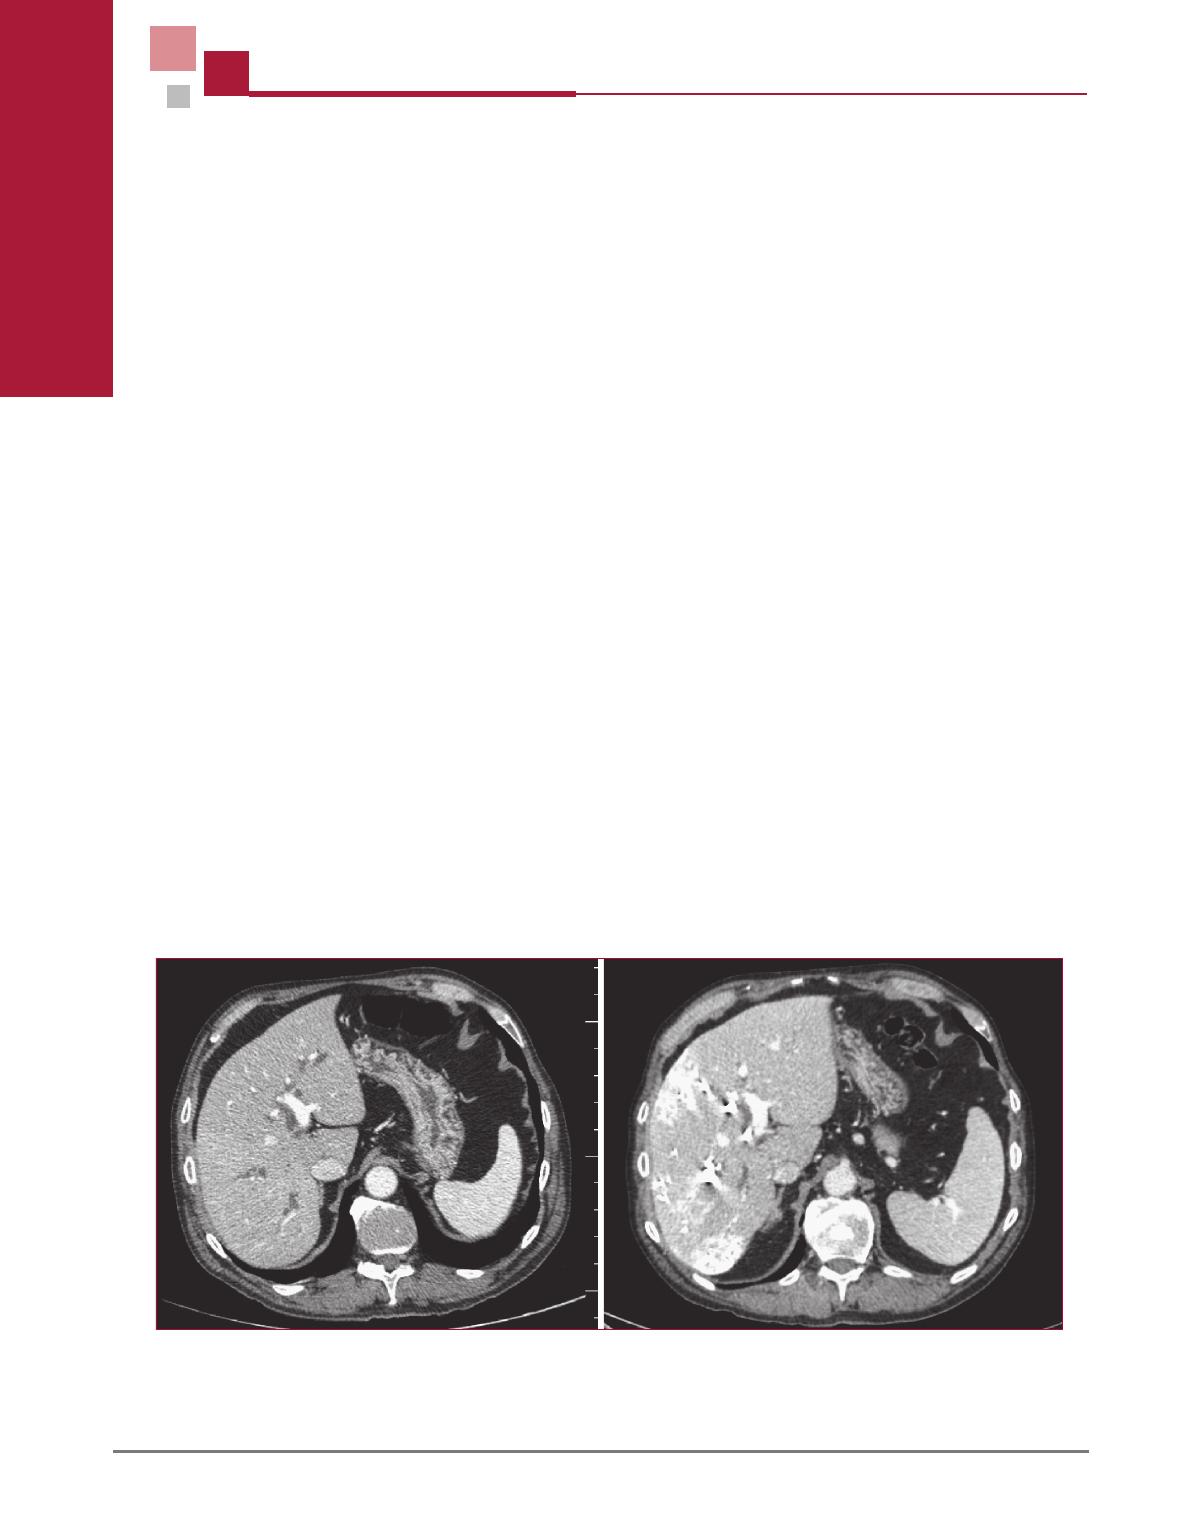

L’intervention chirurgicale avait lieu 4 semaines apr

es

l’embolisation portale droite (volume du lobe gauche

37 %) et consistait en une lobectomie droite associ

ee

a

une r

esection du segment I et de la voie biliaire principale

(figure 5). Un curage ganglionnaire du p

edicule h

epatique

etait effectu

e. Les pertes sanguines

etaient de 600 mL et

le patient n’

etait pas transfus

e.